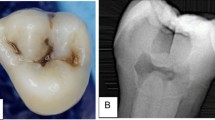

Non-carious human molars were collected with no associated patient identifiers, collection protocol determined as not human subject research, the study was approved by the Independent Ethics Committee of the Affiliated Stomatological Hospital of Nanchang University and all methods were carried out in accordance with relevant guidelines and regulations. All collected molars were informed consent by subjects and/or their legal guardian(s). All methods were carried out in accordance with relevant guidelines and regulations. The extracted human third molars were used within 1 month and preserved in 0.01 M phosphate-buffered saline (pH7.3, ZSGB-BIO Ltd., CHN) at 4 °C. Seventy-nine dentin blocks (6 mm × 2 mm × 2 mm) were obtained from the cervical with a precision cutting machine (Iso Met™ 1000, Buehler Ltd., USA) under water cooling. The test surfaces of the blocks were individually burnished with a series of silicon carbide papers (400, 600, and 1200 grit; 3 M Ltd., USA) for 1 min and cleaned with an ultrasonic cleaning machine for 10 min. Finally, sixty-five dentin blocks with surface microhardness between 60 and 70 (Vickers diamond, 100 g, 10 s; VH1202, Buehler Ltd., USA) were used. Half of the test surface (distal pulp surface) was covered using anti-acid nail varnish. All dentin blocks had to be kept moist to avoid the contraction of the dentin organic matrix during the experiment.